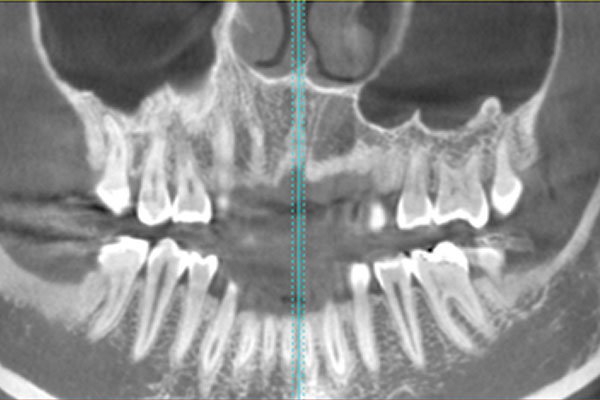

Nei Centri Dentali Zanardi per approfondire lo studio del massiccio facciale e delle arcate dentarie in ottica di programmazione di interventi di implantologia, si ricorre alla Tecnologia 3D.

Questa tecnica di Tomografia Computerizzata, con tecnologia “cone beam”, utilizza un fascio di raggi X di forma conica attraverso il quale si indaga un ampio volume con notevole riduzione di radiazioni rispetto ai sistemi TAC convenzionali.

Oltre che in campo implantologico per valutare le caratteristiche morfo-strutturali, l’altezza e lo spessore dell’osso alveolare nelle sedi di interesse implantare, la Tecnologia 3D è molto utilizzata anche in chirurgia orale e maxillo-facciale, nonché in endodonzia-periodonzia.